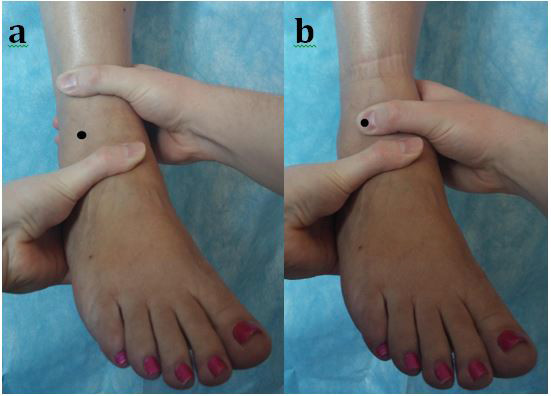

L’ADT est réalisé en fixant la partie distale du segment jambier et en appliquant une force de translation antérieure sur le talon avec l'autre main, comme illustré à la figure 2A.

Le MADT repose sur la même position, mais le pouce de la main tenant le tibia est placé sur la face antéro-latérale du talus pour immobiliser l'articulation tibio-talienne, comme le montre la figure 2B.

Fig 2

Il en résulte que le talus et le tibia deviennent une seule unité et annulent la traduction antérieure du talus du tibia. Tout mouvement se fait donc à partir de l'articulation sous-talienne seule, isolant ainsi la translation antérieure de la tibio-talienne.